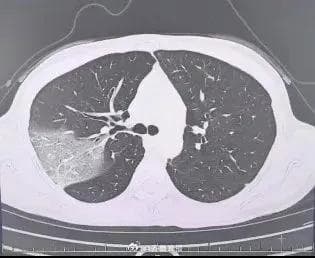

A recent case of a 39-year-old woman from Hangzhou, who developed a severe case of "white lung" after contracting the flu, highlights the importance of timely medical attention and the potential severity of influenza. The woman, a self-described "workaholic," initially attempted to tough out her symptoms, including fever, cough, and shortness of breath, but her condition rapidly deteriorated, leading to a diagnosis of severe influenza with accompanying pneumonia.

Despite being advised to seek hospitalization, the woman initially refused, opting instead for outpatient treatment. However, her condition continued to worsen, and she was eventually admitted to the hospital, where she received intensive treatment, including antiviral medications and oxygen therapy. Fortunately, after seven days of hospitalization, the woman made a full recovery and was discharged.